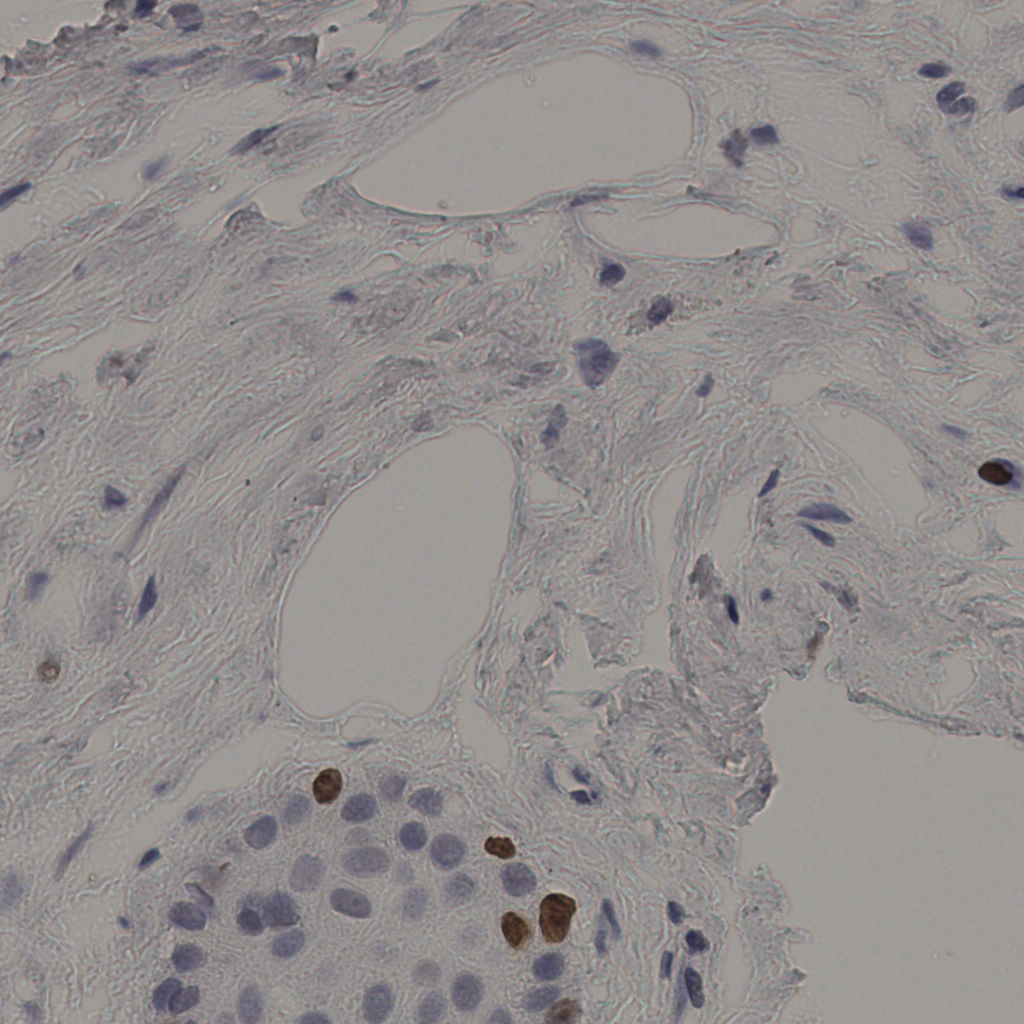

缩略图

标记后

标记前